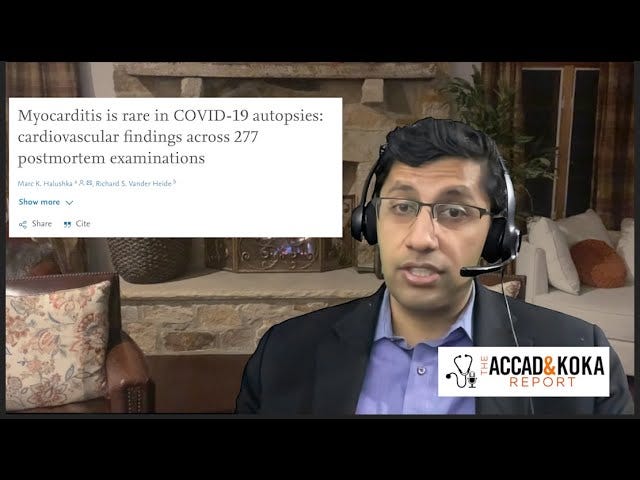

"มันเป็นความผิดพลาดในส่วนของฉัน" การแสดงความอ่อนน้อมถ่อมตนแบบจารีตที่หาได้ยากจากผู้เชี่ยวชาญทางการแพทย์ผู้มีอิทธิพล “ฉันจะไม่ให้มันกับผู้ที่มีความเสี่ยงต่ำอีกต่อไป … มันเป็นความผิดพลาดในส่วนของฉัน” - Dr. Anish Koka

"มันเป็นความผิดพลาดในส่วนของฉัน" การแสดงความอ่อนน้อมถ่อมตนแบบจารีตที่หาได้ยากจากผู้เชี่ยวชาญทางการแพทย์ผู้มีอิทธิพล “ฉันจะไม่ให้มันกับผู้ที่มีความเสี่ยงต่ำอีกต่อไป … มันเป็นความผิดพลาดในส่วนของฉัน” - Dr. Anish Koka หมายเหตุถึงผู้อ่าน: วิดีโอสัมภาษณ์ความยาว 3 ชั่วโมงเต็มกับ Dr. Anish Koka จะมีให้สำหรับสมาชิกแบบชำระเงินในสัปดาห์หน้า

ความอ่อนน้อมถ่อมตนแบบเชิงวิพากษ์เป็นสิ่งที่พบเห็นได้ยากในการแพร่ระบาดของโควิด-19

ดร.อานิช โคคาก็เป็นหนึ่งในนั้น

Koka ดำเนินธุรกิจคลินิกโรคหัวใจชั้นนำในฟิลาเดลเฟีย Koka Cardiology เขาสำเร็จการศึกษาระดับปริญญาจาก Penn State และ Temple University และเป็นแพทย์โรคหัวใจที่ Jefferson Health

ในช่วงเริ่มต้นของการแพร่ระบาด Koka มีความห่วงใยความเป็นอยู่ของครอบครัวเธออย่างแท้จริง เนื่องจากลูกสาวของเธอมีภูมิคุ้มกันบกพร่อง เธอฉีดวัคซีนให้ตัวเองและลูกๆ เมื่อมี mRNA

ในเวลานั้น เขารู้สึกทึ่งกับการทดลองดั้งเดิมของ Pfizer และ Moderna ซึ่งดูเหมือนว่าจะมีประสิทธิภาพและความปลอดภัยที่น่าทึ่ง ในที่สุด เริ่มตั้งแต่เดือนมีนาคม 2021 คลินิกของเขากลายเป็นผู้จัดจำหน่ายวัคซีนป้องกันโควิดจำนวนมาก เนื่องจากจำนวนผู้ป่วยโควิดที่รักษาในโรงพยาบาลเพิ่มขึ้นอย่างน่าตกใจ

สำหรับโปรวัคซีนตายตัว นี่น่าจะทำให้ Dr. Koka พ้นข้อกล่าวหาสมรู้ร่วมคิด "ต่อต้าน Vax" ก่อนที่เราจะเข้าสู่การค้นพบนอกรีตของเขา ผู้ชายคนนี้ไม่ใช่คนโง่ที่รณรงค์ต่อต้านวัคซีนทุกชนิดมานานนับทศวรรษ

ในช่วงหลังของการแพร่ระบาด Koka ตระหนักว่าประสิทธิภาพของวัคซีนระดับดาวที่เคยโด่งดังครั้งหนึ่งไม่ได้เป็นอย่างที่เห็น Koka ยอมรับว่า Alex Berenson เป็นผู้นำในการรายงานข่าวเรื่องวัคซีนป้องกันโควิดที่ถูกปีศาจทำลายได้อย่างไร:

"ฉันจำได้ว่า Alex Berenson เป็นคนแรกที่อ่านข้อมูลของอิสราเอลและรายงานว่าวัคซีนดูเหมือนจะไม่คงอยู่ ทุกคนพูดว่า โอ้ มันไร้สาระ! และ ลองเดาดูสิ อเล็กซ์พูดถูกเกี่ยวกับการป้องกันที่มีขนาดเล็กสำหรับการแพร่เชื้อตามอาการ"

มุมมองของ Koka เปลี่ยนไปอย่างสิ้นเชิงเมื่อความเสี่ยงต่อหัวใจที่เกี่ยวข้องกับโรค mRNA มีความชัดเจนอย่างเจ็บปวด ในช่วงหลายเดือนหลังจากการรณรงค์ฉีดวัคซีนครั้งใหญ่ Koka เริ่มเห็นจำนวนผู้ป่วยโรคกล้ามเนื้อหัวใจอักเสบเพิ่มขึ้น

“แน่นอนว่าผมเห็นจำนวนเคสเพิ่มขึ้น อย่างที่พวกเราหลายคนในแวดวงโรคหัวใจได้เห็น ปฏิเสธไม่ได้ว่า”

หลังจากพิจารณาข้อมูลเกี่ยวกับโรคกล้ามเนื้อหัวใจอักเสบที่เกิดจากวัคซีนในช่วงสองปีที่ผ่านมา Koka ถือว่าการให้วัคซีนป้องกันโควิดแก่คนหนุ่มสาวที่มีสุขภาพดีเป็นความผิดพลาดครั้งใหญ่

"ฉันโยนไลน์ปาร์ตี้ออกไป แล้วข้อมูลก็ออกมา"

เขายอมรับว่ามนต์ที่ "ปลอดภัยและมีประสิทธิภาพ" ที่เขานำมาใช้ในขณะนั้นซึ่งเป็นส่วนหนึ่งของอุดมการณ์ศาสนาหลอกของลัทธิโควิดนั้นมีข้อบกพร่องและเป็นอันตราย

“วิ่งไปรอบๆ โดยบอกว่า 'ปลอดภัยและมีประสิทธิภาพ' และมอบให้กับเด็กอายุ 17 ปี เนื่องจากผู้ป่วยส่วนใหญ่ในการทดลองวัคซีนอายุยังไม่ถึง 17 ปี ฉันไม่ยุติธรรมในทางเทคนิค” เลย

ที่บอกว่าปลอดภัยและมีประสิทธิภาพเพราะว่าในกลุ่มนั้นมีคนไม่มากพอที่จะพูดแบบนั้น” เขากล่าวเสริม

โชคดีที่โคคาฉีดวัคซีนส่วนใหญ่เป็นผู้สูงอายุกลุ่มอายุอ่อนแอไม่ใช่คนหนุ่มสาว

” ฉันเป็นผู้เล่นตัวเล็ก.. .ฉันคิดว่าฉันยิงไปทั้งหมด 800 หรือ 900 ช็อต อาจจะเป็นชายหนุ่มห้าคน ฉันไม่คิดว่าฉันจะฉีดวัคซีนเด็กอายุ 15-17 ปี อาจมีบางคนอายุ 20-25 ปี หรืออาจจะ 10 ขวบก็ได้”

ส่วนเรื่องอันตรายต่อหัวใจวัยรุ่น โคกะเล่าว่า “ฉันรอดมาได้เพราะอัตรา [ของกล้ามเนื้อหัวใจอักเสบ] อยู่ที่ประมาณ 1 ใน 5,000” “

อยู่ในกลุ่มที่มีความเสี่ยงสูงสุด กลุ่มเรียล 20-25 มันอาจจะต่ำกว่านั้นก็ได้...ใช่แล้ว ผมหนีไปแล้ว" เขากล่าวเสริม

อย่างไรก็ตาม โคกะไม่มีภาพลวงตาว่าการศึกษาทางคลินิกเกี่ยวกับโรคกล้ามเนื้อหัวใจอักเสบอย่างเคร่งครัด (ซึ่งมีรายงานอย่างเป็นทางการ) ) เป็นเพียงสิ่งเดียวที่ต้องกังวล มีเหตุผลที่ดีที่ต้องกังวลเนื่องจากผลที่ไม่พึงประสงค์ต่อระบบหัวใจเพิ่มเติม

เมื่อพูดถึงการศึกษาที่ครอบคลุมที่น่าตกใจในประเทศไทยซึ่งพิจารณาความเสียหายของกล้ามเนื้อหัวใจตายในเด็กอายุ 13 ถึง 18 ปี - การตรวจ EKG และวัดระดับโทรโปนินก่อนและหลังการฉีดไฟเซอร์ครั้งที่สอง - Koka กล่าวว่า: "ถ้าคุณมีกิจกรรมเกี่ยวกับหัวใจมากขนาดนี้ - 3 กรณีของภาวะกล้ามเนื้อหัวใจอักเสบทางคลินิกและระดับโทรโปนินที่มีนัยสำคัญ 4 กรณี -เพิ่มขึ้นจากวัยรุ่น 300 ราย - ดังนั้นเราต้องระมัดระวังอย่างมากเมื่อเราเผยแพร่สิ่งนี้"

“ฉันหมายความว่าคุณควรชัดเจนเกี่ยวกับผลประโยชน์” เขากล่าวเสริม

การศึกษาของไทย หากเป็นตัวแทน บ่งชี้ถึงการบาดเจ็บที่หัวใจจำนวนมากในระดับประชากรในกลุ่มอายุน้อยที่มีสุขภาพดี

“การศึกษานี้ระบุว่า หากเราแพร่กระจายวัคซีนนี้ไปยังเด็กอายุ 13 ถึง 18 ปีหลายล้านคน เราจะพบผู้ป่วยโรคกล้ามเนื้อหัวใจอักเสบทางคลินิกจำนวนมาก”

“มันเป็นวัคซีนที่ออกฤทธิ์ต่อหัวใจมาก” เขากล่าวเสริม

เมื่อพิจารณาถึงการตอบสนองต่อโรคระบาดและการแจกจ่ายวัคซีน mRNA ในคลินิกโรคหัวใจของเขา Koka ได้แสดงความถ่อมตัวอย่างจริงใจ

“ฉันจะไม่ให้มันกับคนที่มีความเสี่ยงต่ำอีกต่อไป” เขากล่าวเรียบๆ “นั่นเป็นความผิดพลาดในส่วนของฉัน”